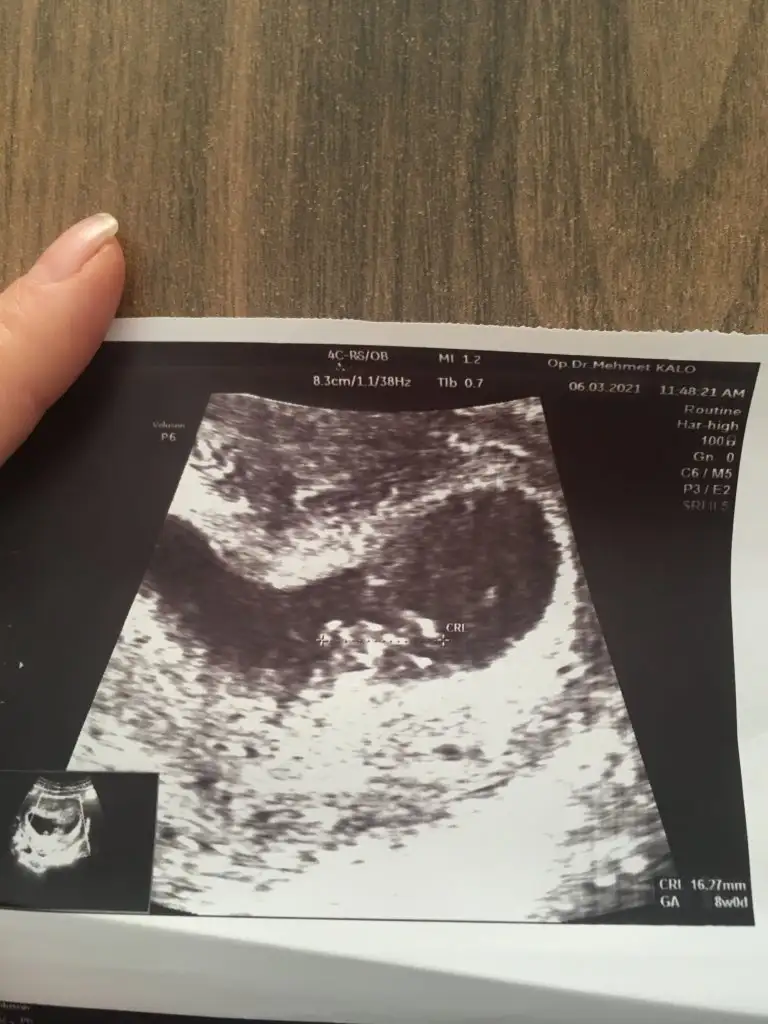

8 hafta çok erken ama bana da bakabilir misiniz